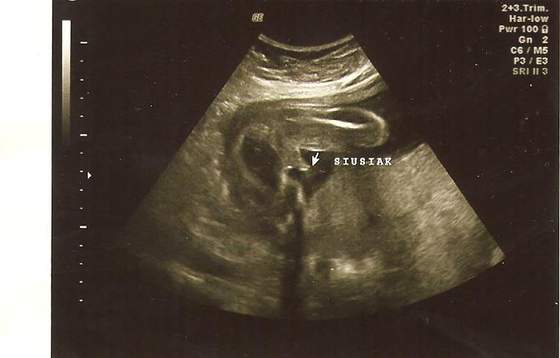

To USG mojego pierwszego syna. Uważam że nie można tego pomylić z niczym innym, więc jak lekarz w 13tc widzi coś takiego to chyba nie ma złudzeń :-D

siusiak 001.jpg

• siusiak 001.jpg

17 KB · Wyświetleń: 77